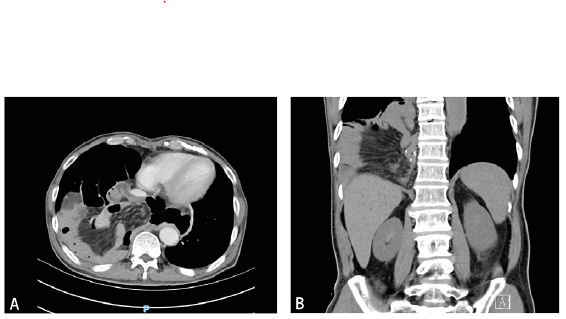

The patient, a 71-year-old male with a BMI of 23.4 kg/m2, underwent a gastroscopy on March 9, 2023, which revealed a cardia mass. Pathology confirmed adenocarcinoma. Preoperative thoracoabdominal Computed Tomography (CT) showed intact bilateral pleura without thickening, no pleural effusion, and an intact diaphragm (Figures 1A & 1B). On March 6, 2023, he underwent a laparoscopic radical total gastrectomy, D2 lymph node dissection, and esophagojejunostomy with Roux-en-Y reconstruction at our hospital. Histopathology revealed moderately to poorly differentiated gastric adenocarcinoma G3, with tumor staging of ypT3, ypN0 (0/22), L0, V0, R0, cM0. On postoperative day 17, a follow-up thoracoabdominal CT showed localized thickening of the bilateral pleura, a small amount of right pleural effusion, and the esophagojejunostomy located within the thoracic cavity (Figures 1C & 1D). The patient was discharged cured and received adjuvant chemotherapy thereafter.

Figure 1: Preoperative and postoperative thoracoabdominal CT scans of the patient who underwent laparoscopic total gastrectomy.

A-B. Preoperative images; C-D. Postoperative images.